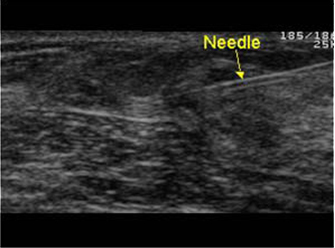

ε) Για να πραγματοποιήσουμε επεμβατική πράξη, όπου καθοδηγούμε τη βελόνα με τους υπερήχους για βιοψία συμπαγούς μορφώματος (εικόνα 4) ή εκκένωση κύστης (εικόνες 5,6) ή τοποθέτηση συρμάτινου οδηγού σε ογκίδιο για την ακριβή εξαίρεσή του χειρουργικά.

(Εικόνα 6)